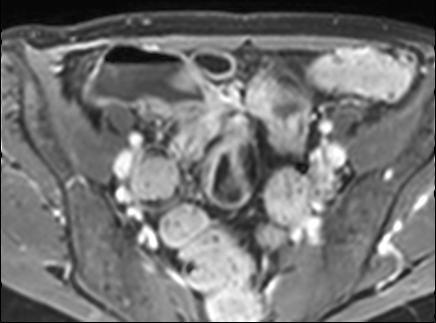

Rò

Đường xoang và đường rò là các biến chứng thường gặp ở bệnh nhân mắc bệnh Crohn.

Cả hai đều ngấm thuốc rõ rệt trên chuỗi xung T1W sau tiêm gadolinium.

Đường rò có thể biểu hiện dưới dạng cấu trúc phân lớp kiểu ‘đường ray tàu hỏa’ hoặc như một cấu trúc tuyến tính ngấm thuốc.

Đường rò có thể đi từ quai ruột này sang quai ruột khác, đến một tạng rỗng khác hoặc ra da.